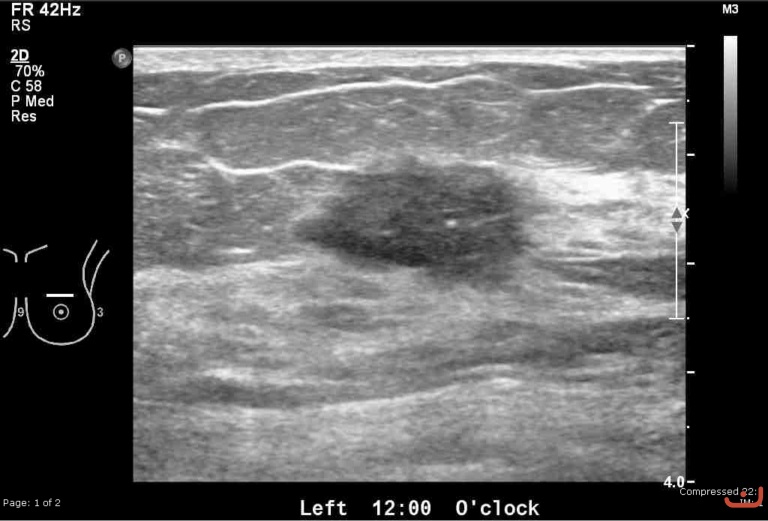

Malignant solid mass

Date

Thursday, 30 April 2015

176.96 KB (768 x 521 px)